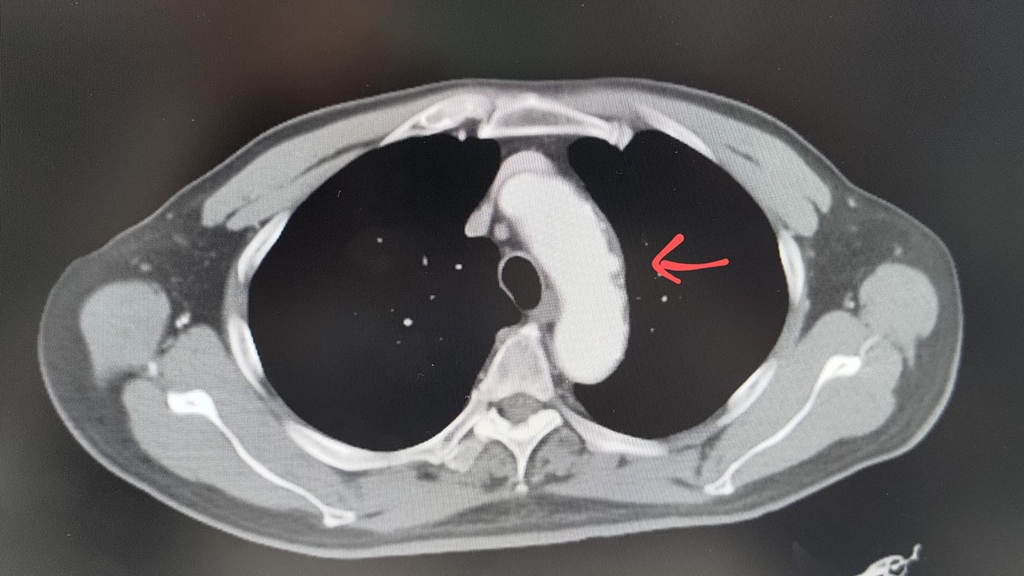

周宜群提醒,目前國內病毒性肝炎引起的肝癌雖然還是占最大宗,但是脂肪肝引起的肝癌愈來愈威脅國人健康,尤其是飲酒引起的脂肪肝,已經是國人肝硬化、肝癌的重要原因,提醒大家不要喝酒。